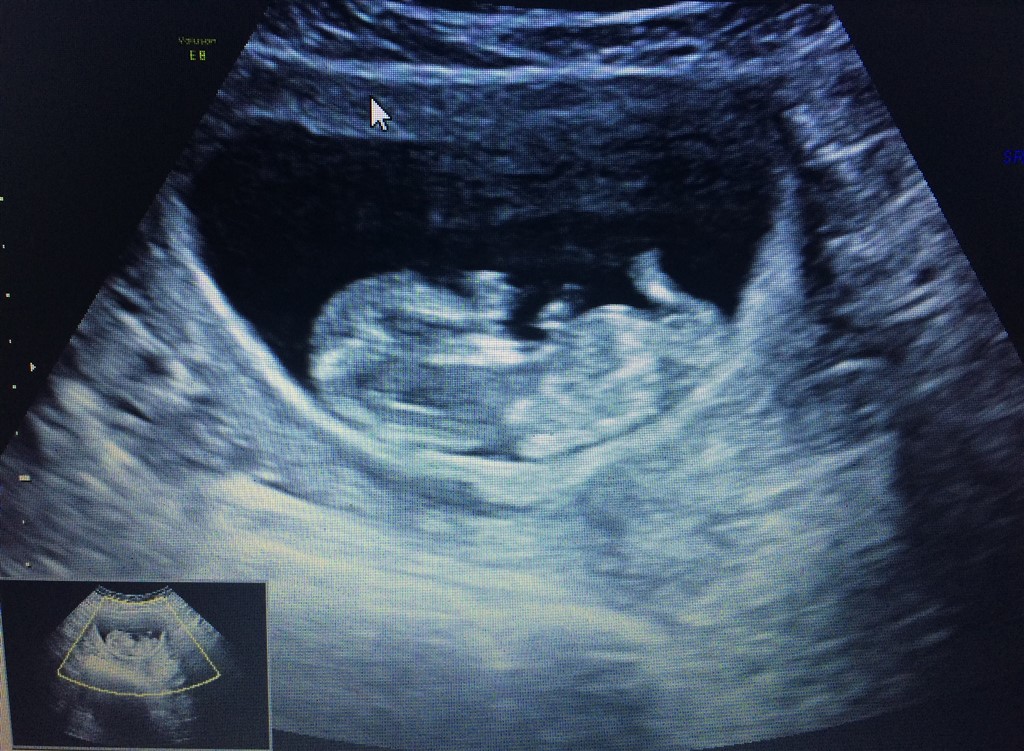

Er i uge 11 på scanningen. Og ved der sidder mange eksperter herinde aner ikke hvad man skal kigge efter  tør i give et bud?? På et af billeder bagfra kan man tydeligt se en tap. Men hun sagde det både kunne være tissemand og klit

Relativt flad pande og burgerlinjer i ryggen på billede 3, umiddelbart en pige